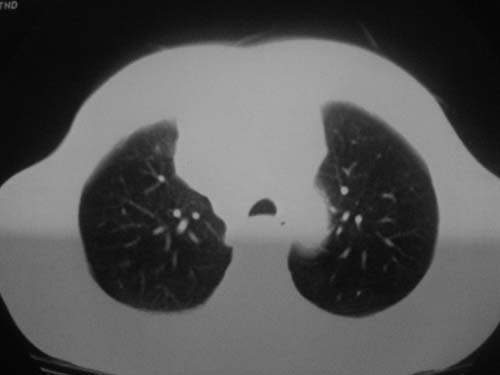

以下是引用科室第一人在2010-3-25 20:30:00的发言:[br]1:纵膈肿瘤性病变,恶性胸腺瘤可能性大伴纵膈右肺门淋巴结转移,右侧胸腔积液。[br]2:右侧肺门肿瘤性病变,纵膈淋巴结转移,右侧胸腔积液。右下叶转移。

以下是引用子期在2010-3-25 21:00:00的发言:[br]先考虑右中央型肺癌伴转移。

以下是引用江广1996在2010-3-25 22:49:00的发言:[br]通常肺癌向纵隔转移多见,纵隔肿瘤向肺内转移少见(有的表现为向肺内侵润)。本例以一元论考虑:右中心型肺癌并纵隔淋巴等多处转移。[br][br][本贴已被 江广1996 于 2010-3-25 22:50:07 修改过]

以下是引用yangyudong333在2010-3-26 6:43:00的发言:[br]“冰冻纵膈”,考虑纵膈淋巴瘤伴肺内及胸膜侵润。